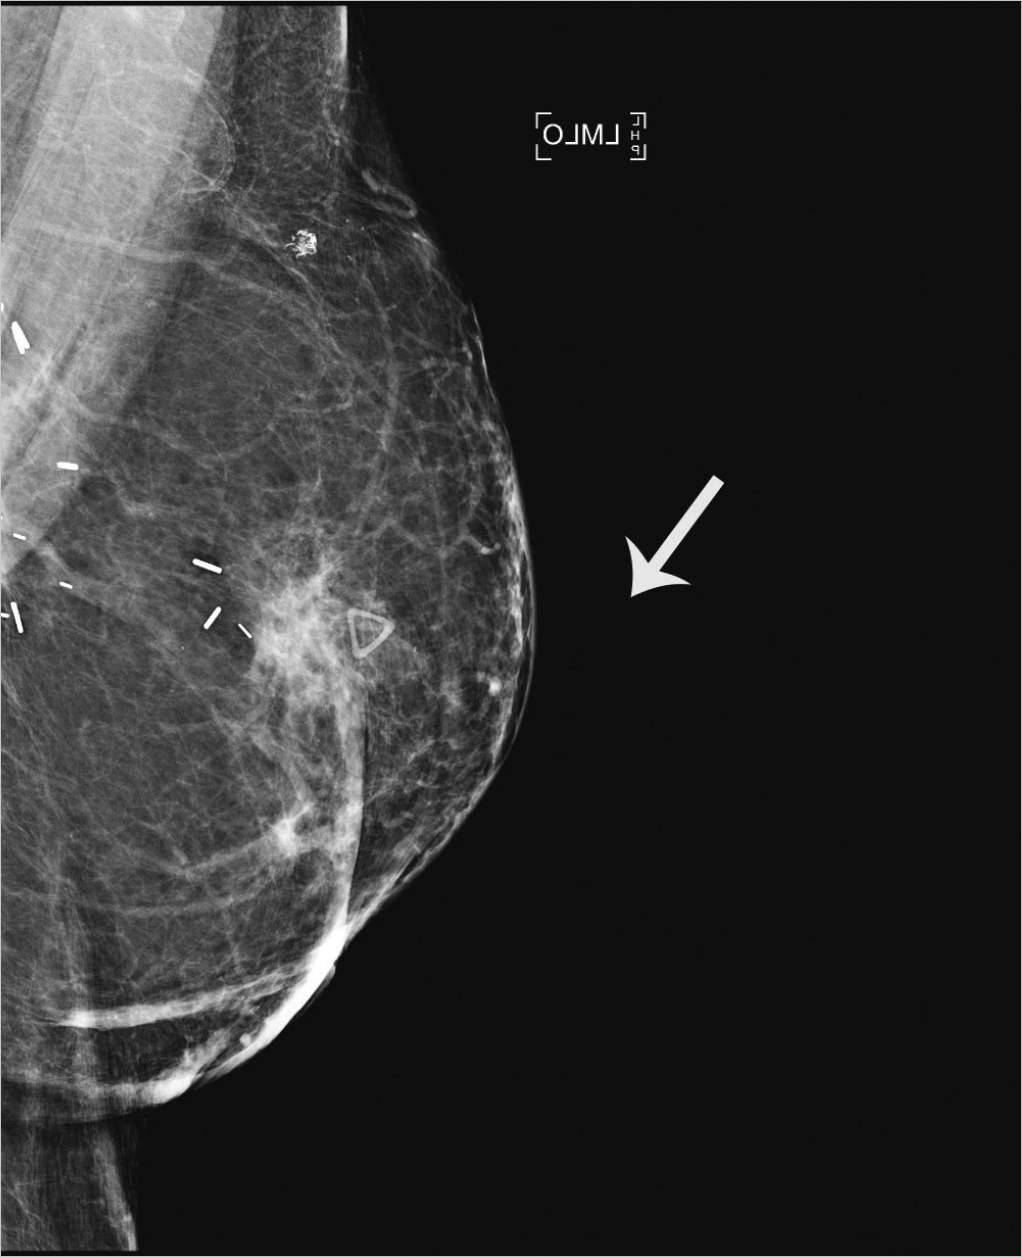

The sensitivity of physical examination of autologous reconstruction is lower than that seen with implant reconstruction. Deep chest wall recurrences often avoid detection until symptoms develop. Autologous reconstruction causes less impairment of mammographic tissue visualization. Benign mammographic findings after transverse rectus abdominis muscle (TRAM) flap reconstruction include fat necrosis, lipid cysts, calcifications, lymph nodes, and epidermal inclusion cysts (▶Fig. 4.3). Breast cancer recurrences in autologous tissue reconstruction are mammographically similar to that of primary tumors (▶Fig. 4.4). Proponents of surveillance mammography feel that screening breast cancer patients with autologous reconstructions can detect nonpalpable recurrences before clinical examination. Helvie et al evaluated surveillance mammography in 113 patients after TRAM flap reconstruction. Six patients underwent biopsy for suspicious mammographic findings and two LRs were detected. Two patients in the study group went on to develop recurrences that were detected by physical examination. There was one false-negative mammogram resulting in a sensitivity of 67% and specificity of 98% for surveillance mammography after TRAM flap reconstruction.

Surgical options following LR after breast reconstruction depend on the location and number of metastatic deposits and previous treatment. Imaging of the reconstructed breast and body scans are necessary to delineate the extent of tumor involvement (▶Fig. 4.4). Isolated LRs can be treated with removal of as much reconstructed tissue as necessary to achieve negative margins. Adjuvant chest wall radiation is usually administered (▶Fig. 4.5).